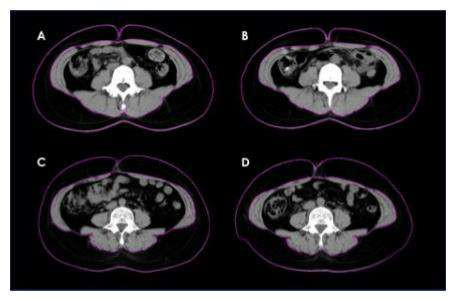

Giảm chỉ số kích thước vòng bụng thông qua hình cảnh đo bằng CT-Scan trước và sau 10 tuần bổ sung DNF. Mỡ bụng được đo bằng chụp cắt lớp vi tính (CT) trong nhóm chứng ở W0 (A) và W10 (B) và trong nhóm DNF-10/1000 ở W0 (C) và W10 (D)